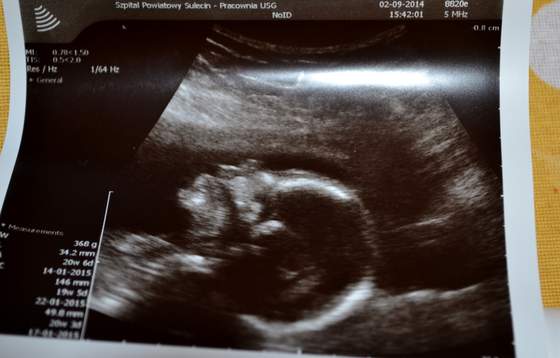

A oto nasze nie do końca zidentyfikowane dziecię :-)

Z profilu i z rączką przy uchu

DSC_0472.jpgDSC_0477.jpg